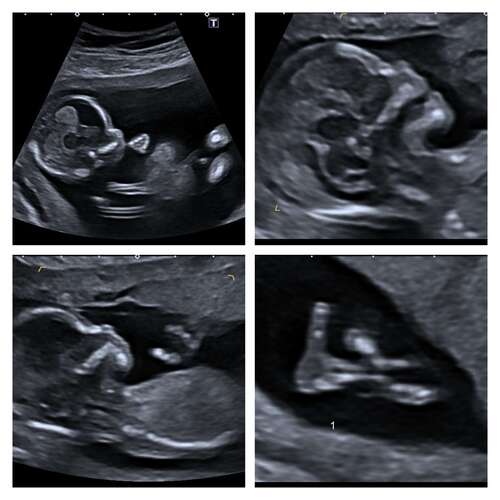

Dit is mijn 13 weken echo met 13+4 dagen. Wat denken jullie wat het wordt q ...

Als ik de skull theorie erbij pak zou ik zeggen meisje